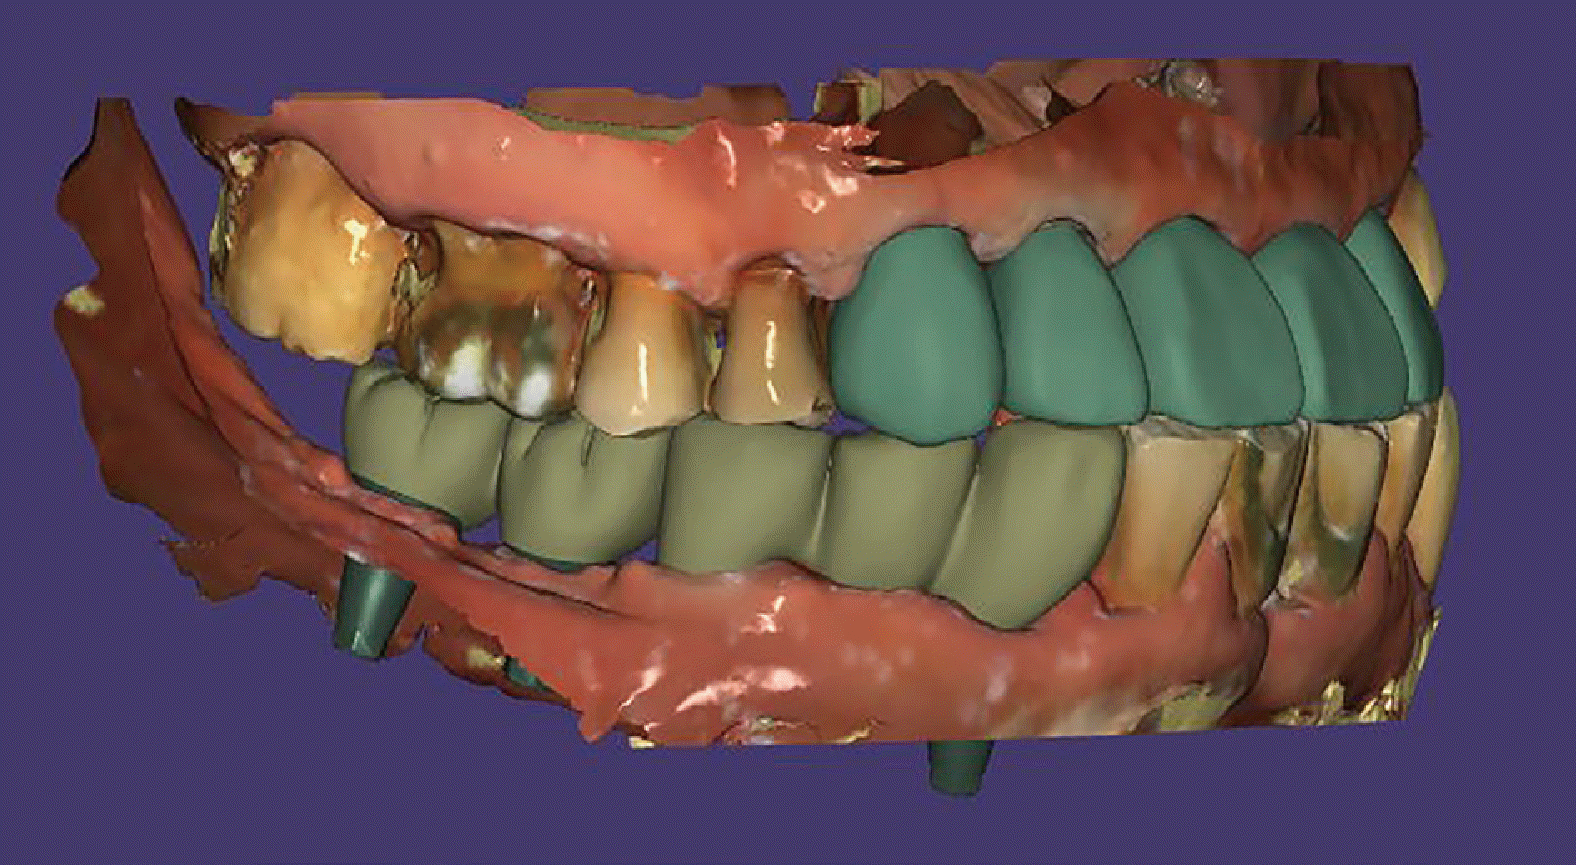

Fig. 4

Images of the provisional crowns for both anterior and posterior teeth are presented. (A - C) Delivery of provisional crowns on maxillary anterior and mandibular posterior areas in a proper CR position, (D) A digital image depicting the provisional state is shown.

Osstem TS III fixtures (Osstem Implant Co., Seoul, South Korea) were placed at #36 and #37, and Dentis S-Clean SQ-SL implants (Dentis Co., Daegu, South Korea) at #34, 35, 43, 45, 46, and 47. Immediately post-surgery, Highness® base abutments were connected with 30 Ncm torque, followed by attachment of Highness® scan bodies using hand torque. Digital impressions of the maxillary and mandibular dentitions, including a buccal bite scan reflecting the established anterior bite stop, were obtained using Primescan (Sirona Dental Systems GmbH, Bensheim, Germany) and analyzed with Exocad software (Exocad GmbH, Darmstadt, Germany). The following day, polymethyl methacrylate (PMMA) Highness® provisional restorations were delivered with hand torque, establishing partial group function occlusion during lateral excursions (Fig. 3, 4).